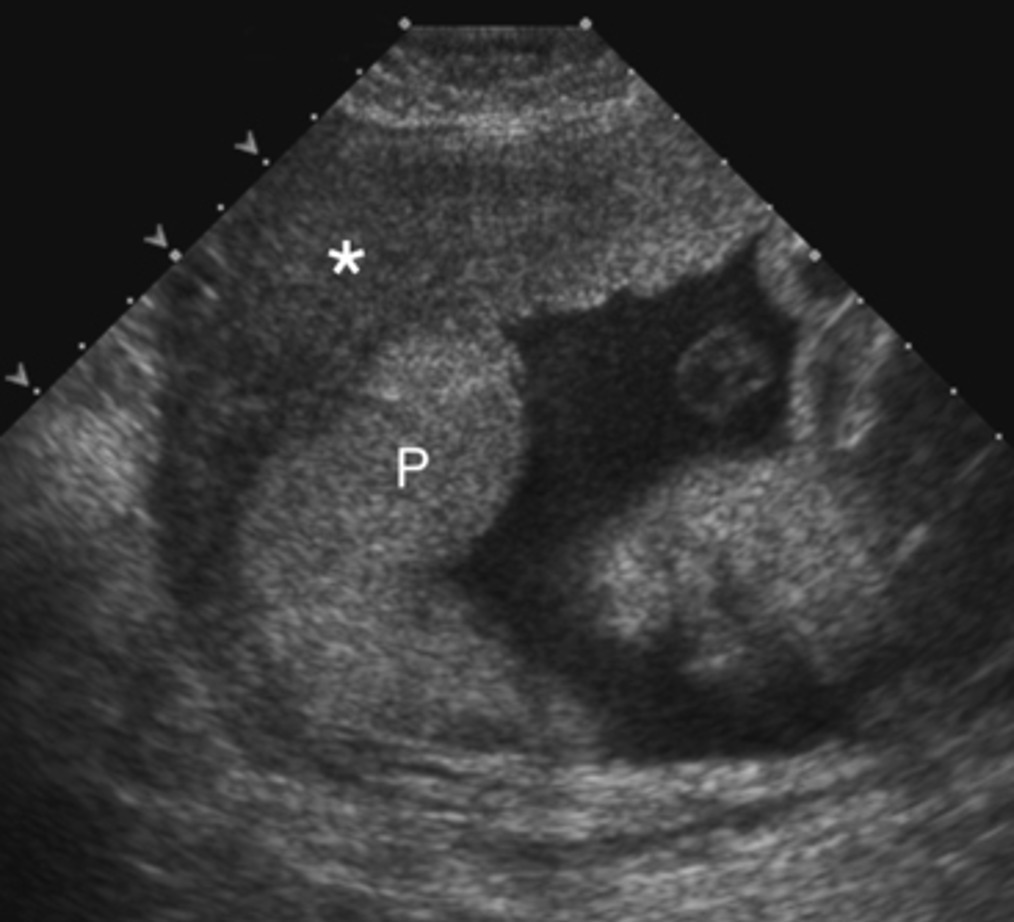

Vous poursuivez votre examen. L’échographie endovaginale vous montre ce cliché (figure 4). L’étude des annexes (trompes et ovaires) ne retrouve pas d’anomalies.

Figure 4 (source : S. Khiat)